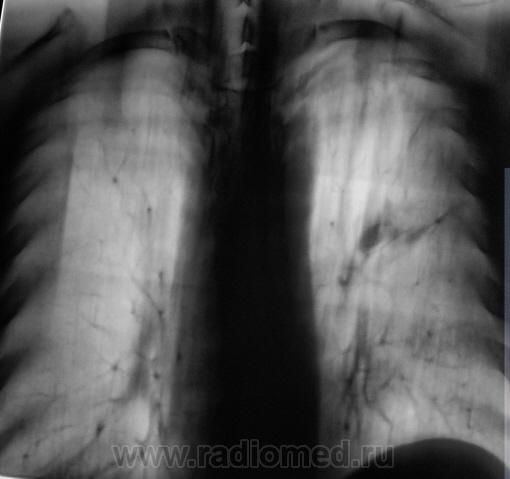

При расшифровке флюорограмм пациент "взят на контроль". Жалоб пациент не предъявляет. Подняли "архив", флюорограмма за 2009 г. - "норма".

Произвели стандартное дообследование.

Томограммы.